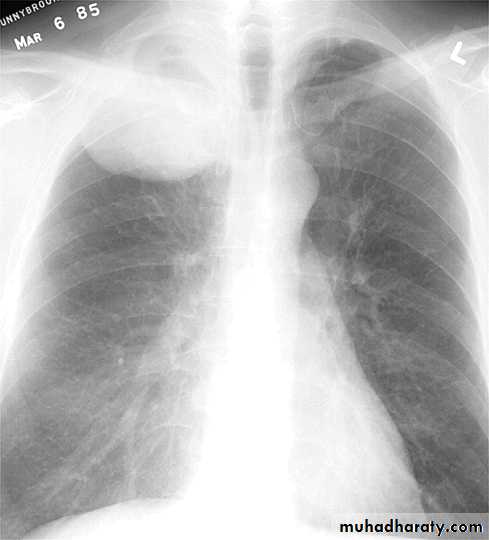

Massive pleural effusion

Lamellar pleural effusion